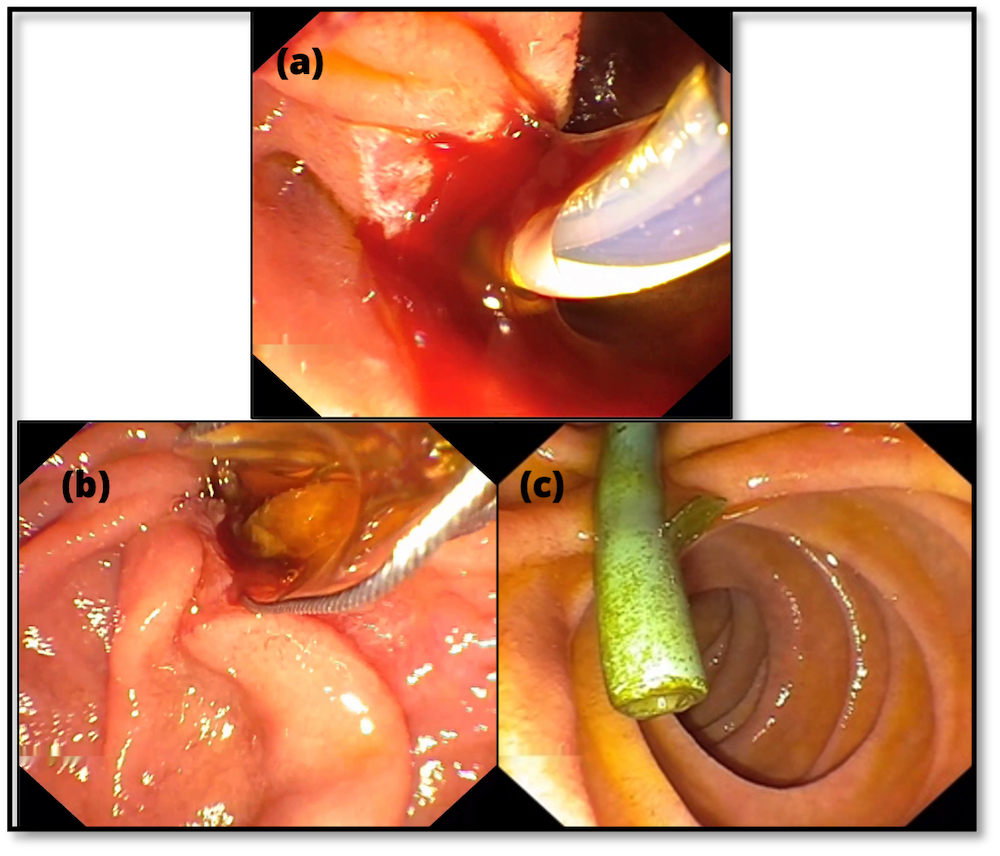

Ergebnis: Die Hepatikojejunostomie konnte erfolgreich endoskopisch dargestellt werden. Es zeigten sich mehrere ausgeprägte Gefäßkonvolute im Sinne von Varizen. Nach gezielter Punktion einer Varize erfolgte die Applikation von drei mit Faser versehenen Coils (je 7 mm). Zusätzlich wurde eine Portion Histoacryl injiziert. Im Anschluss wurde eine weitere Varize punktiert und mit zwei Coils (8 mm, ohne Faser) sowie zwei Portionen Histoacryl versorgt. Endosonographisch zeigte sich im Farbdoppler ein sehr gutes Akutergebnis. Endoskopisch traten keine akuten Komplikationen auf.

Abbilung 1: Endoskopisches Bild der Ösophagusvarizen (A) und der Varizen im Bereich der Hepatikojejunostomie (B)